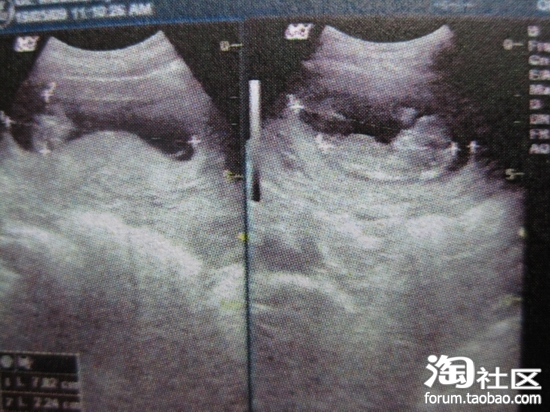

11W+4D,看到小宝宝躺着的舒服样子